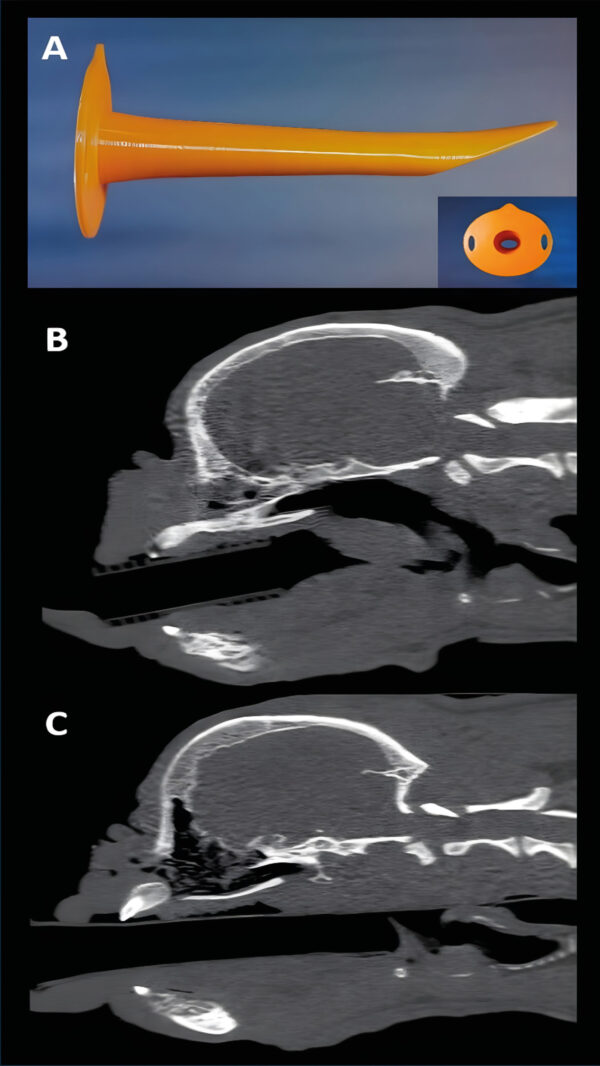

En veterinaria está estudiado y comercializado un dispositivo adaptado para su utilización principalmente en razas braquiocefálicas. Esta cánula consiste en un cilindro que en su parte proximal puede adaptarse a un circuito anestésico para proporcionar oxígeno. Se continúa con un cilindro recto cuya parte distal es un bisel largo que es capaz de desplazar dorsalmente el paladar blando y ventralmente la base de la lengua. De esta manera, no dificulta la respiración y el paciente puede ventilar eficazmente (imagen 2 y vídeo 1). Por lo tanto, es de gran ayuda en este tipo de pacientes, en los que asegura el flujo del aire a las vías respiratorias de forma poco invasiva, aunque requerirá algo de sedación para que el animal la tolere sin tener reflejo deglutorio (imagen 2).

Se pueden utilizar tanto para antes de la inducción anestésica (asegurando que la preoxigenación es optimizada) como en la recuperación anestésica, ya que los animales suelen tolerar el dispositivo hasta que están muy recuperados, por lo que el colapso de las estructuras laríngeas es menos probable. Su principal limitación es que no protege la vía aérea, por lo que, si hay secreciones o regurgitación, este material puede pasar dentro de la tráquea.